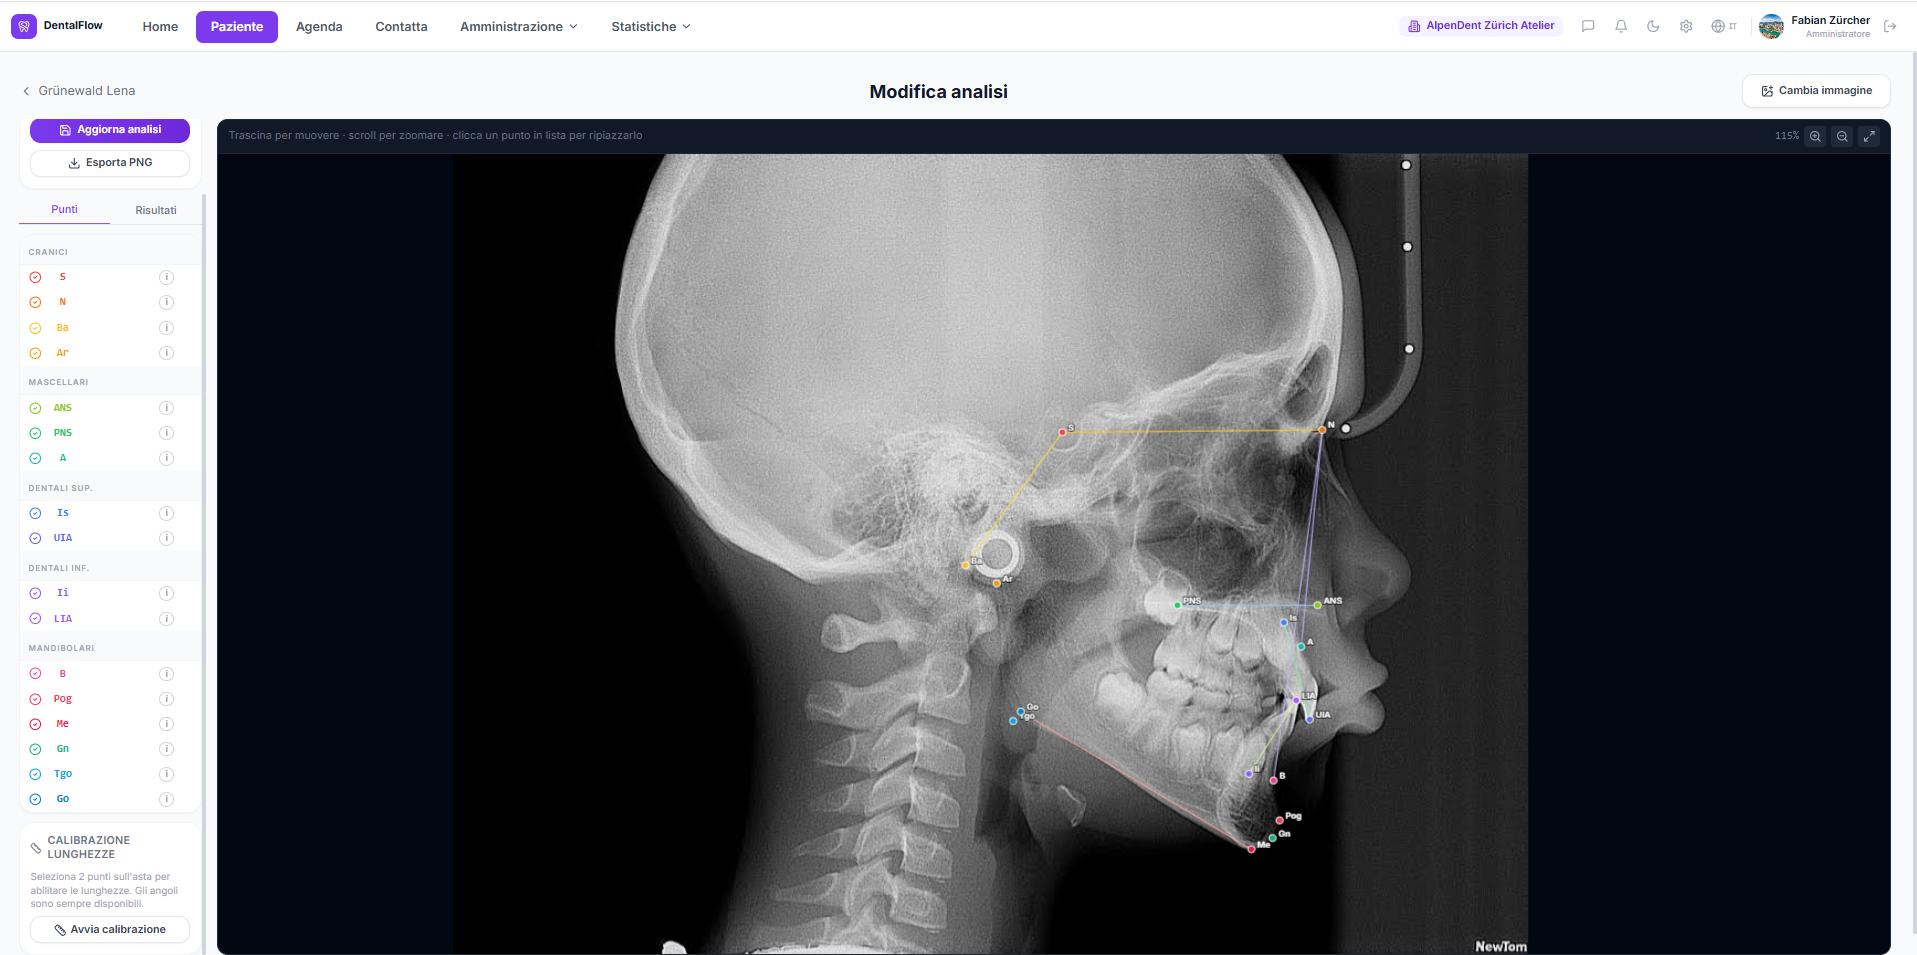

Carica la teleradiografia, marca i punti cefalometrici. Angoli e distanze calcolati in automatico.